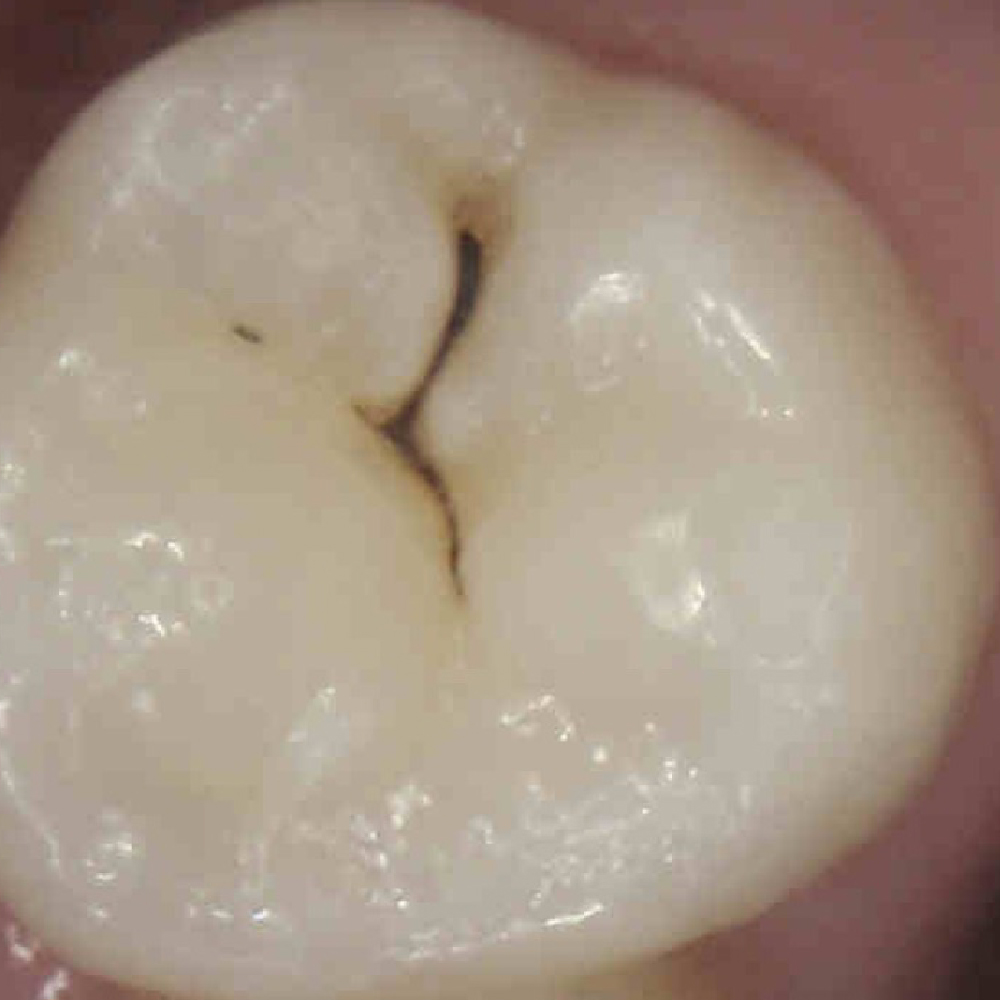

IMAGE 3

Can you differentiate?

0

SOUND

Quiz Image Overlay Overlay

Prevention/Treatment Pathway Options

Low Caries Risk – Regular Fluoride and monitoring

Medium to High Risk – Fissure sealant or silver diamine fluoride

Supported by:

• Fluoride for prevention (all teeth)

• OHI/Education

• Regular screening with Calcivis Imaging

The staining in the fissures is either arrested or remineralized or it is staining, and whilst it is not showing any caries activity, you may opt to intervene based on the patient’s caries risk or level of compliance.